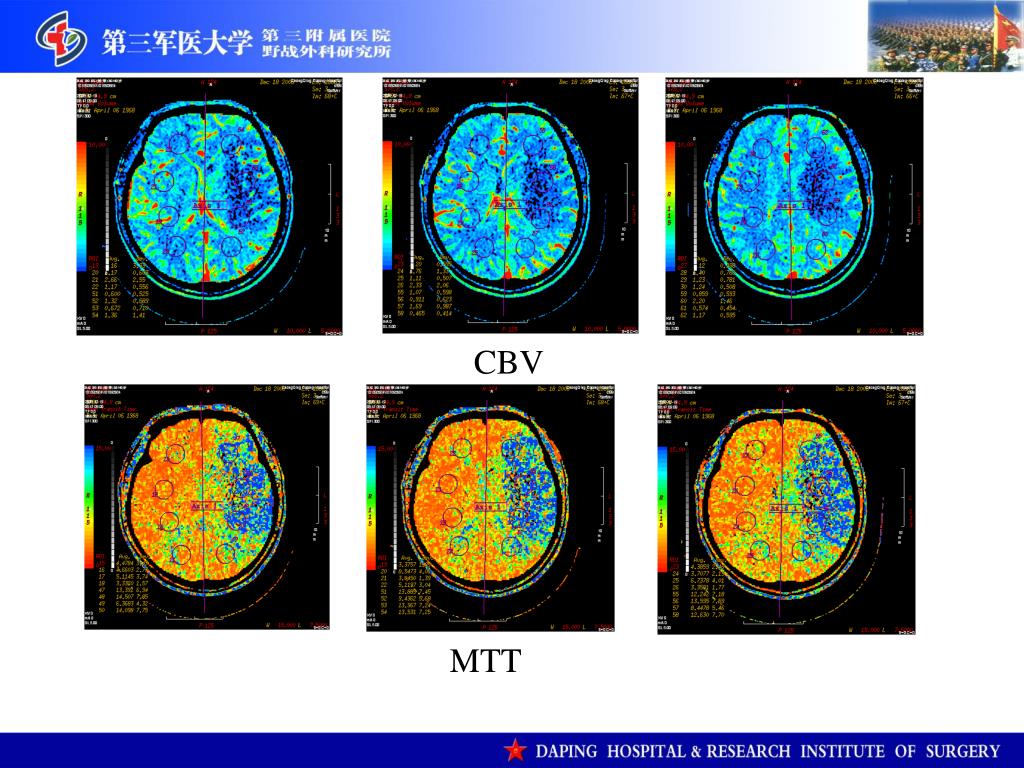

5. 2009.12.18头颅CTP提示“左侧额颞叶及基底节区广泛血流灌注降低,表现为脑血流量弥漫性降低”2009.12.18头颅CTP提示“左侧额颞叶及基底节区广泛血流灌注降低,表现为脑血流量弥漫性降低” BF

6. CBV MTT